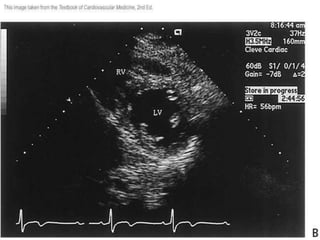

• Hay 4 posiciones del transductor para los

exámenes en eje corto del VI.

• El plano l da una vista de la punta del

corazón

• La posición 2 es una vista a nivel de los

músculos papilares.

• El plano 3 esta a nivel de la válvula mitral.

• El plano cuatro da una vista a nivel de la

válvula aórtica.